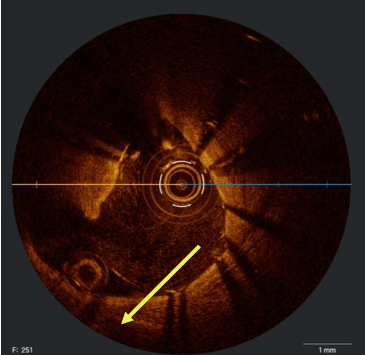

In view of this complication and the clinical instability of the patient, extraction of the device with a coronary snare was attempted but was unsuccessful (Figure 3). The access route was then changed to the femoral artery using an Amplatz left 6F catheter, and a Sion guidewire was advanced to the distal segment of the right coronary artery with the support of a 135-cm FineCross microcatheter (Terumo). This was followed by dilatation using a Sapphire II PRO balloon (OrbusNeich) (Figure 4) with catheter extension and anchoring of the balloon until 2 new everolimus-eluting stents (2.5 x 40 mm and 3.0 x 15 mm) could be advanced (Figure 5). Upon post-dilation of the noncompliant balloon, the previous stent and ballon were successfully crushed, obtaining a good final angiographic result (Figure 6). The procedure was completed with intracoronary optical coherence tomography, which confirmed adequate stent expansion and apposition, as well as the crushing of both the stent and the previous balloon (Figures 7-11).